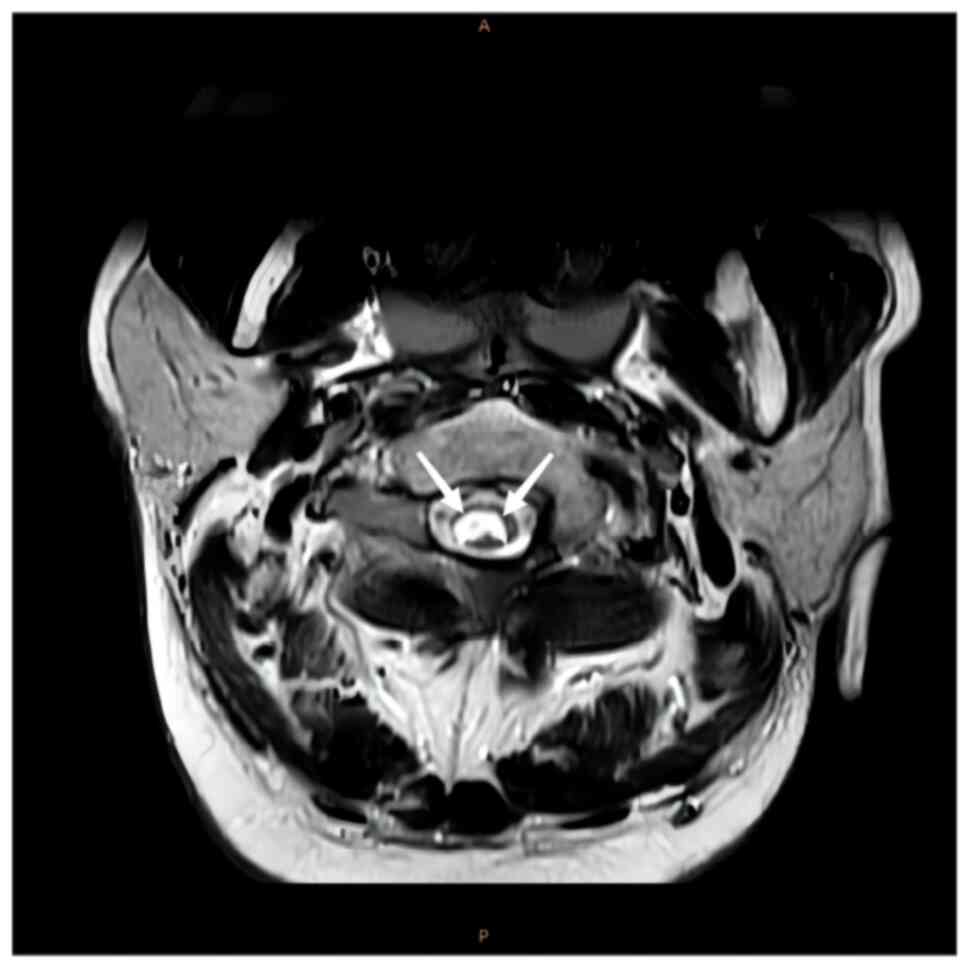

intramedullary signal with a high signal (Figs. 1 and 2). Axial images indicated that the

lesions mainly occupied the posterior portion of the spinal cord in

a ‘figure-eight sign’ (Figs. 3 and

signs were positive. SCD typically occurs in the cervical spinal

cord and the lesions usually cause a ‘figure-eight’ change in the

posterior cord.